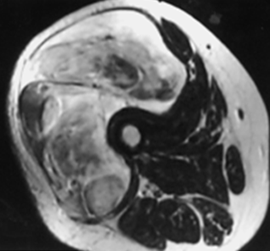

Fig 49 B. Estadiaje.

A: RM axial en T1 y B: RM axial en STIR. Tumoración de tejidos blandos en el muslo, que cruza compartimientos e invade los grupos musculares, correspondiendo a sarcoma de tejidos blandos.